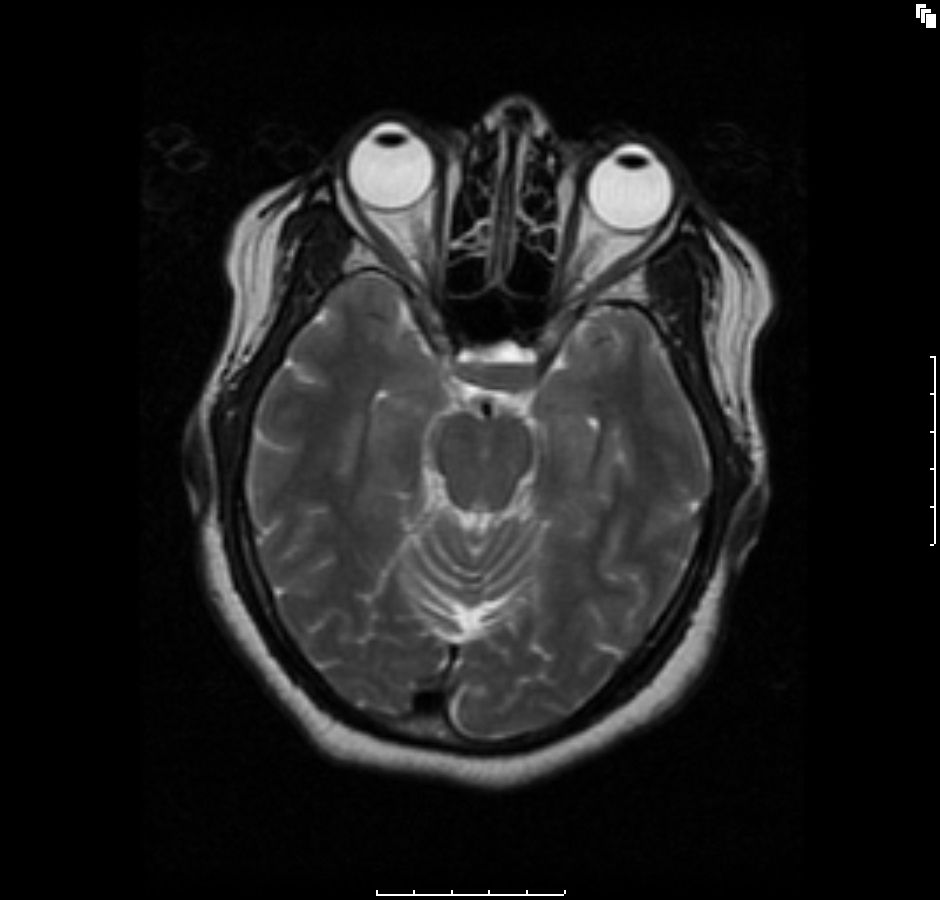

Figure A2: Axial T2-weighted image showing a fluid-fluid level consisting of a hypointense bottom layer and a hyperintense upper layer (red arrow) depicting a hemorrhagic fluid debris level.

The initial brain scans were obtained 6 months after her initial diagnosis (3 months into her pregnancy) and revealed a hemorrhagic pituitary macroadenoma (Figures A1-4). The patient recollects that a week before the scan, she suffered an episode of severe headache with visual disturbance of the right eye. She did not seek medical attention at the time but did keep an appointment for the brain imaging the following week. At the time of the imaging, she reported that her symptoms had fully resolved.